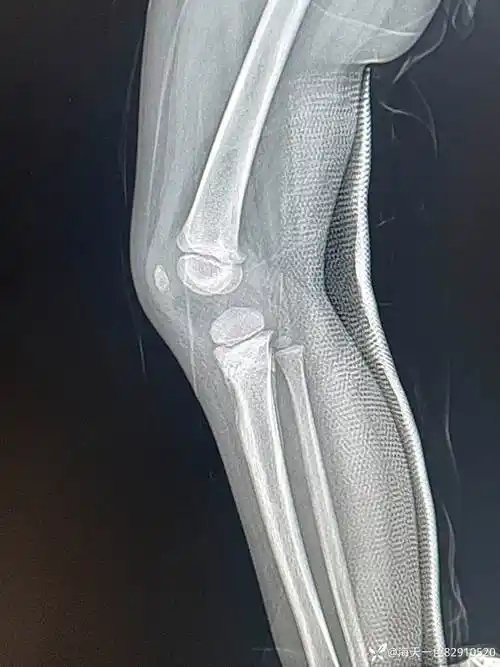

儿童胫骨近端骨折